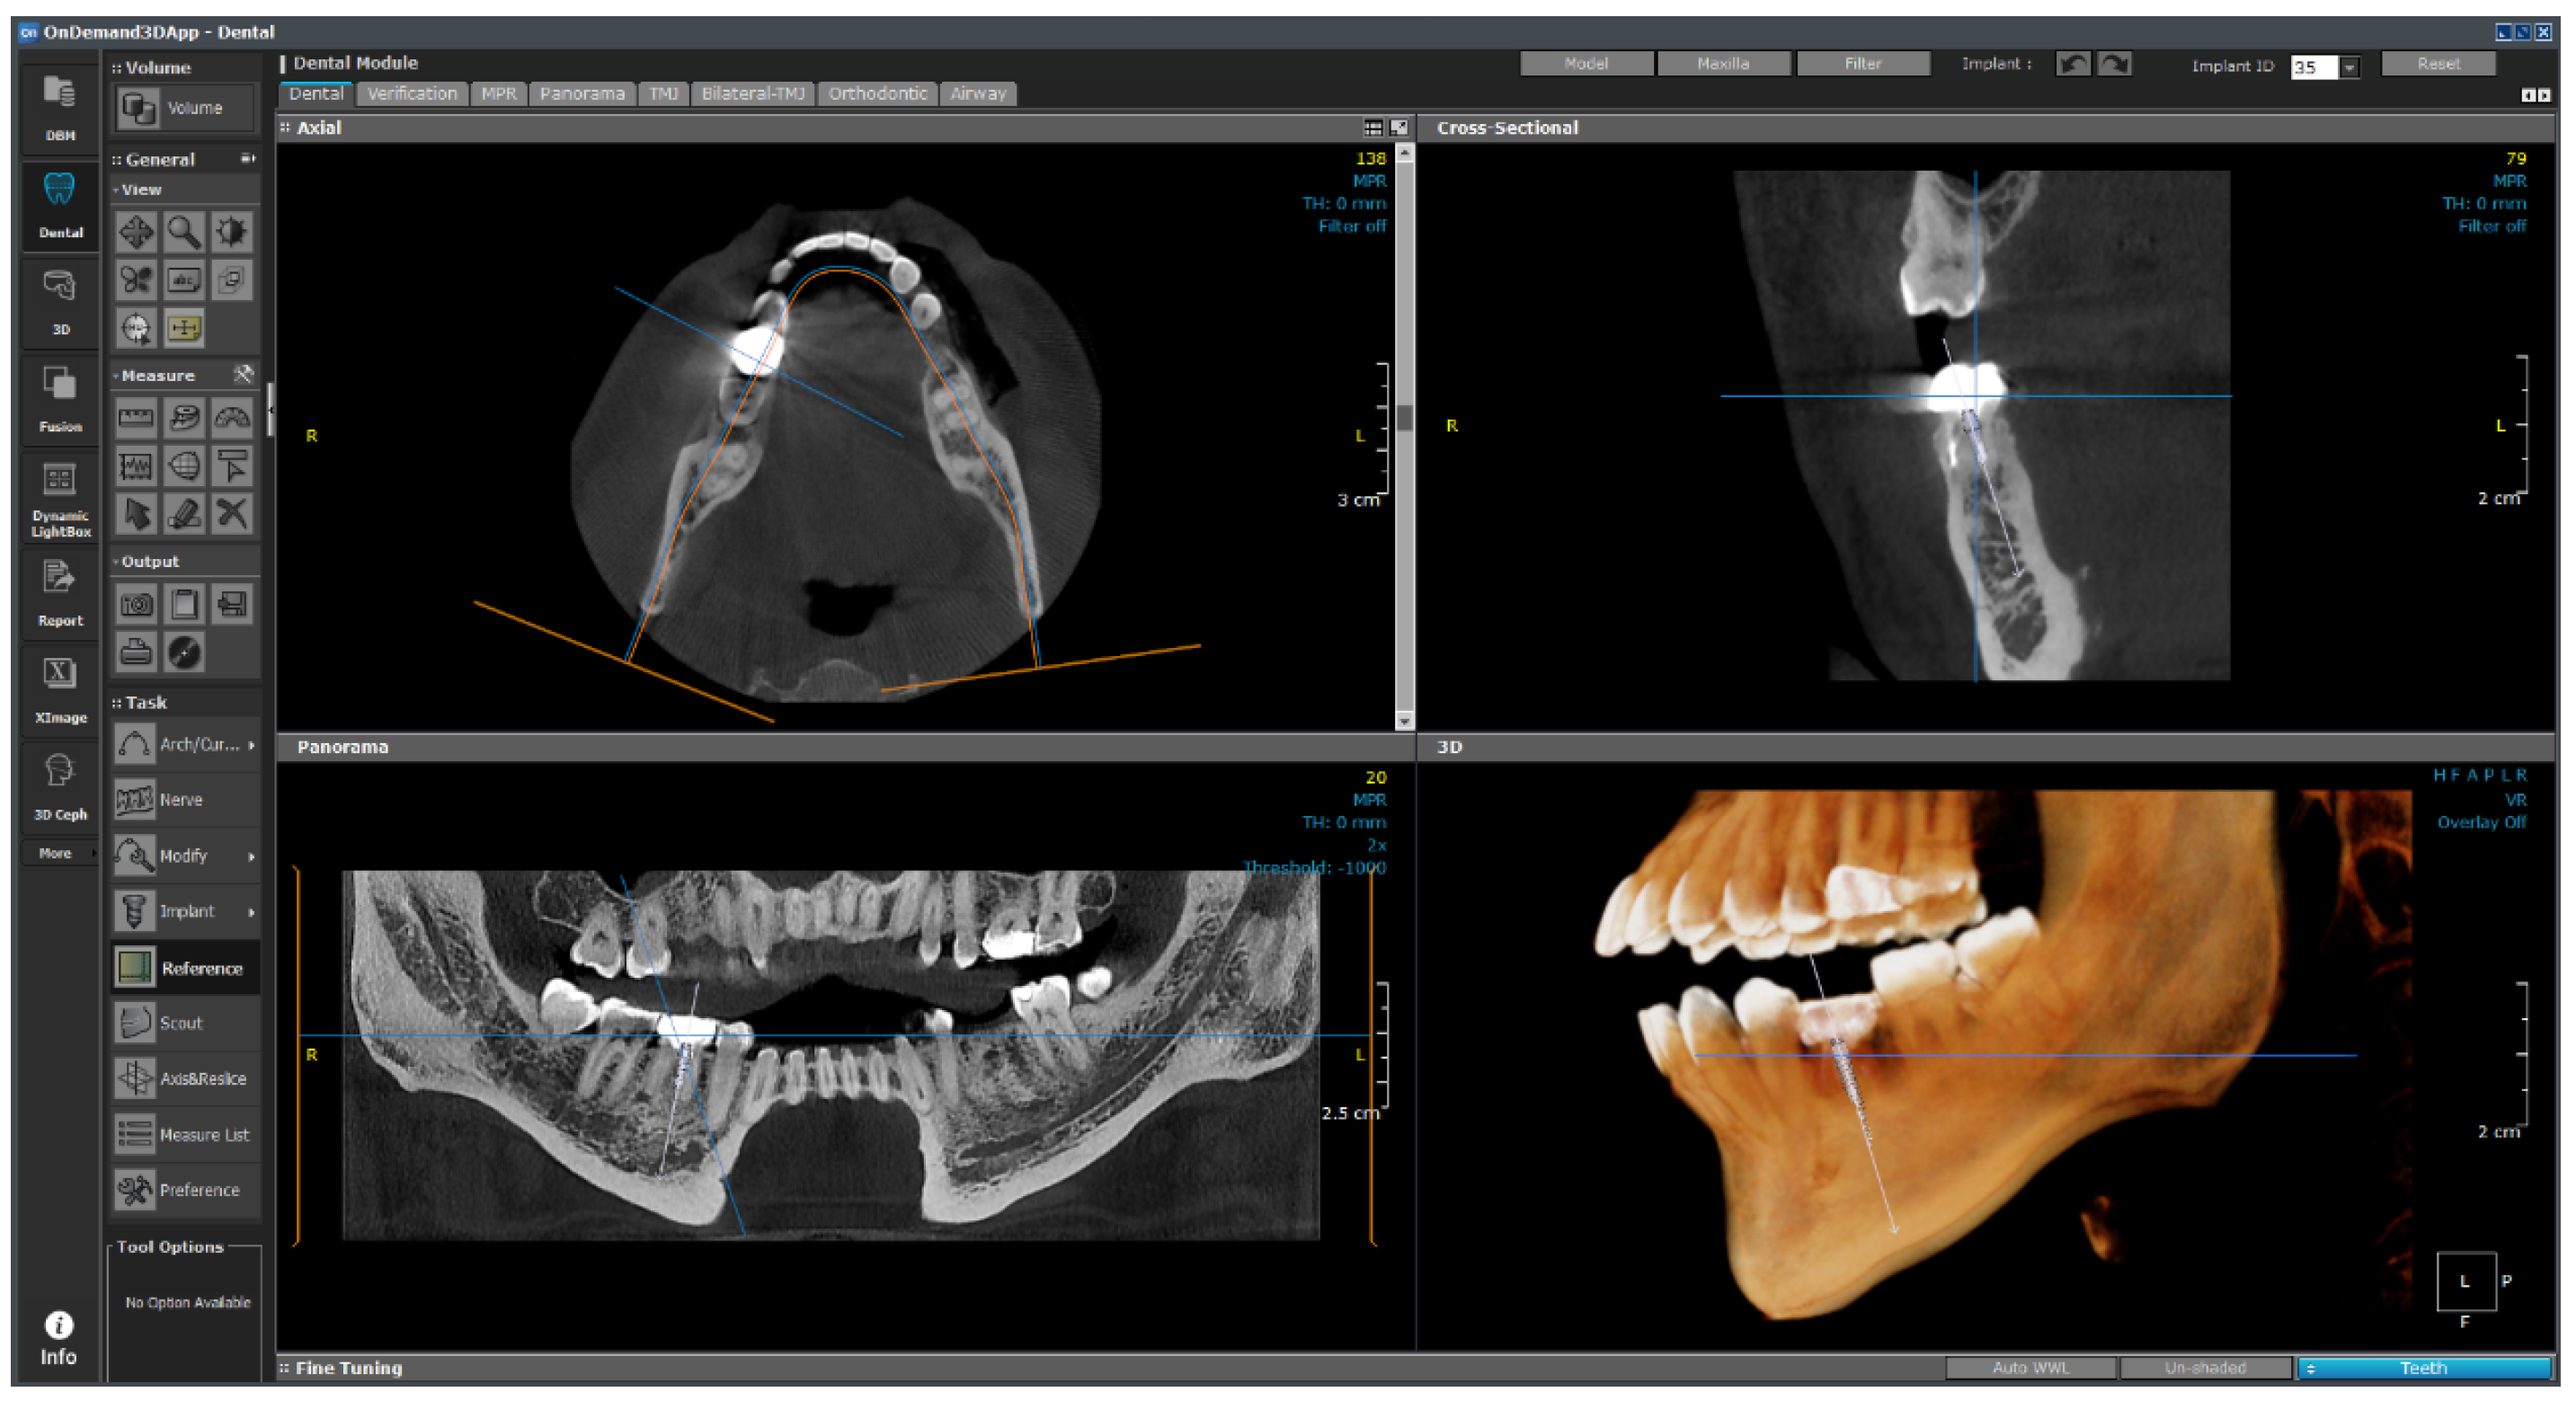

As shown in Figure 27, the empty space between the teeth is determined from the photographic data, and the implant is placed. The six variables are subsequently changed, as shown in Figure 28, and are input in the 1-D CAE solver for automatic calculation. The stress level in the cortical bone is displayed in green for under 40 MPa and in red for higher.

In the future, we plan to subdivide the range based on the experiences of actual dentists and present it as a gradation from safe (green) to dangerous (red).

The calculated values were loaded into OnDemand3D software, and the position and angle of the implant, as determined from the data obtained through the video, were applied to the parameter column. The 1-D CAE solver was automatically calculated when the implant length, diameter, and Young’s modulus of the cancellous bone were entered according to the patient’s condition; subsequently, the results were derived. If the maximum stress generated in the cortical bone was more than 40 MPa, the implant was displayed in red; if it was less than that, the implant was displayed in green. The stress value under the condition was derived such that stability could be confirmed visually.

Figure 27. OnDemand3D featuring implant planning and surgical guide design.

Figure 28. Real-time implant FEA results using 1-D CAE solver.